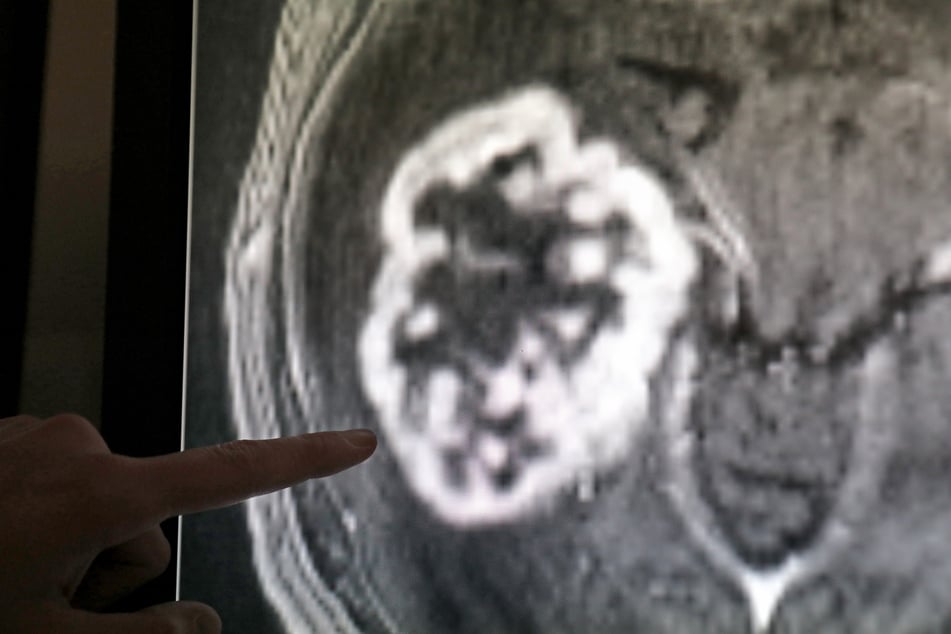

Gut ein Drittel aller Krebstoten in Sachsen-Anhalt (2716) starb den Angaben zufolge an Krebsleiden an Verdauungsorganen, etwa Darm-, Bauchspeicheldrüsen- und Magenkrebs. In 1509 Fällen führte Lungenkrebs zum Tod, davon waren in 958 Fällen Männer betroffen.